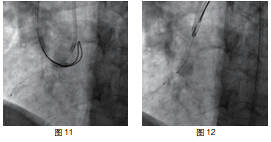

患者RCA为完全闭塞病变,用6F.EBU 3.5导引导管经股动脉对侧造影显示间隔支到RCA远端的侧枝循环,如正向无法开通右冠状动脉可改逆向开通。用JR6F-4导引导管两条pilot-50导引导丝在微导管支持下,用平行导丝技术通过闭塞病变(图3)。分别用Sprinter 1.5 mm×15 mm和2.5 mm×15 mm球囊扩张后RCA开口出现严重夹层,在RCA近端置入Partner 3.0 mm×36 mm支架(图4)。但支架远端仍有严重狭窄,IVUS证实RCA全程弥漫病变,用原2.5 mm球囊扩张后支架远端后,支架远端出现螺旋夹层。拟通过近端支架置入另一Partner 2.75 mm×36 mm支架,但支架无法通过近端支架,头端卡在第一个支架内,在反复用力推送过程中导引导管、导丝自RCA中脱出、将支架球囊弹出,支架球囊撤出体外后发现支架已脱落。透视RCA开口至桡动脉全程,及导引导管内,未发现脱落支架。迅速将原JR4导引导管到位,置BMW导丝到RCA远端,保证RCA开通(图5),IVUS证实导丝全程在真腔内。用原2.5 mm球囊扩张RCA远端以便器械通过(图6)。血管内超声检查提示RCA中段螺旋夹层,撕裂深及血管外膜(图7)。右冠近端支架膨胀、贴壁良好(图8)。将超声导管回撤至右冠状动脉开口处,可见脱落支架卡在右冠状动脉近端支架开口处(图9)。拟取出支架,为预防取出支架过程中RCA急性闭塞,在RCA远端置入BuMA 2.5 mm×30 mm和3.0 mm×30 mm支架,近端支架和原RCA开口处支架未连接(图10)。将Snare圈套器经原作为对侧造影的6F.EBU 3.5导引导管伸出(图11),调整位置,将脱落的支架套住。同时将RCA内的导丝保留,RCA近端支架内预置一3.0 mm×10 mm高压球囊,以保护在取出脱落支架时RCA开口处支架不受影响(图12)。在回撤圈套器时遇到较大阻力,反复推拉,在取出脱落支架的同时将置入RCA开口已释放的的Partner 3.0 mm×36 mm支架带出(图13~14)。RCA开口出现螺旋夹层,但未闭塞。立刻重新置入导丝,IVUS证实导丝在真腔内,在RCA近端分别置入BuMA3.0 mm×25 mm和3.5 mm×20 mm支架,RCA无残余狭窄,血流TIMI3级(图15)。